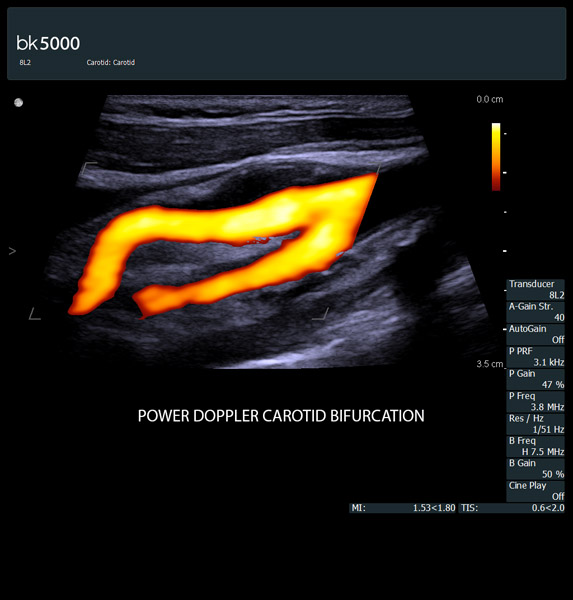

From the simplest diagnostic imaging to the most critical interventional procedures, every clinical situation has its own set of unique challenges. The bk5000 offers a full suite of innovative technologies and advanced controls and adjustments to help you achieve the best possible image quality, across many applications.